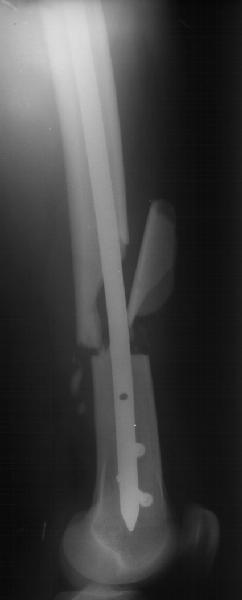

THX for all suggestions and wonderful clinical cases. I just performed closed nailing with static locking. Images attached. We still haven't yet availavble thick locking bolts so use 4,5 cortical screws instead so i don't plan to hurry with weight bearing. Comments are welcome.

Agree with delayed weightbearing. Bucholtz wrote an article with reference to distal femur fractures within 5 cm. of the proximal of the two distal locking holes...50% of the intact femur strength was necessary by healing to prevent a fracture through the nail at the level of the hole in the rod.